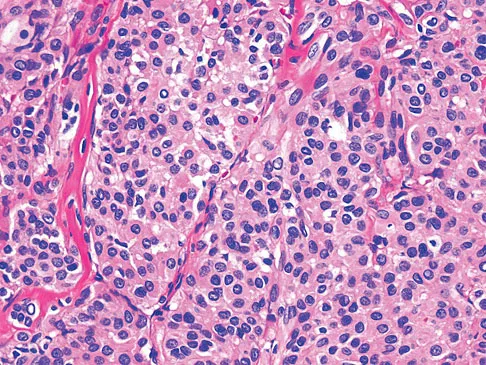

Question 27

A 55-year-old woman has slowly increasing pain at the distal end of her little finger that is exacerbated by cold temperatures. She denies any history of trauma to her hands and is employed as a school teacher. The histology of the resected specimen is shown in Figure 71. What is the most likely diagnosis?